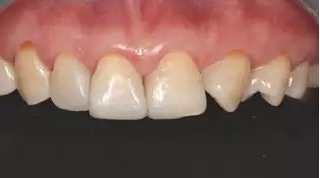

病例分享|復(fù)合樹脂微創(chuàng)美學(xué)修復(fù)關(guān)閉上前牙間隙

術(shù)前上前牙正面照